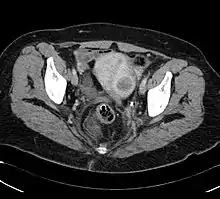

A CAT scan of a uterine fibroid

Fibroids are a particularly important condition to mention when discussing racial disparities in menstrual health. Uterine fibroids are significantly more likely to occur in black women, with 9 out of 10 black women being diagnosed with fibroids before the age of 50.[173] Black women also face higher rates of adverse symptoms, like extreme pain and heavy menstrual bleeding. Impacts on black women are further worsened by the fact that 42 percent of black women wait four years or more before seeking out treatment for fibroids, compared to 29 percent of white women.[174] Fibroids have immense consequences in terms of cancer risk, as black women who have fibroids have shown to be 40 percent more likely to have some form of endometrial cancer.[175] Analogously, it has been demonstrated that black women are equally as likely to have endometriosis, but are significantly less likely to be diagnosed with the disease compared to white women.[176]